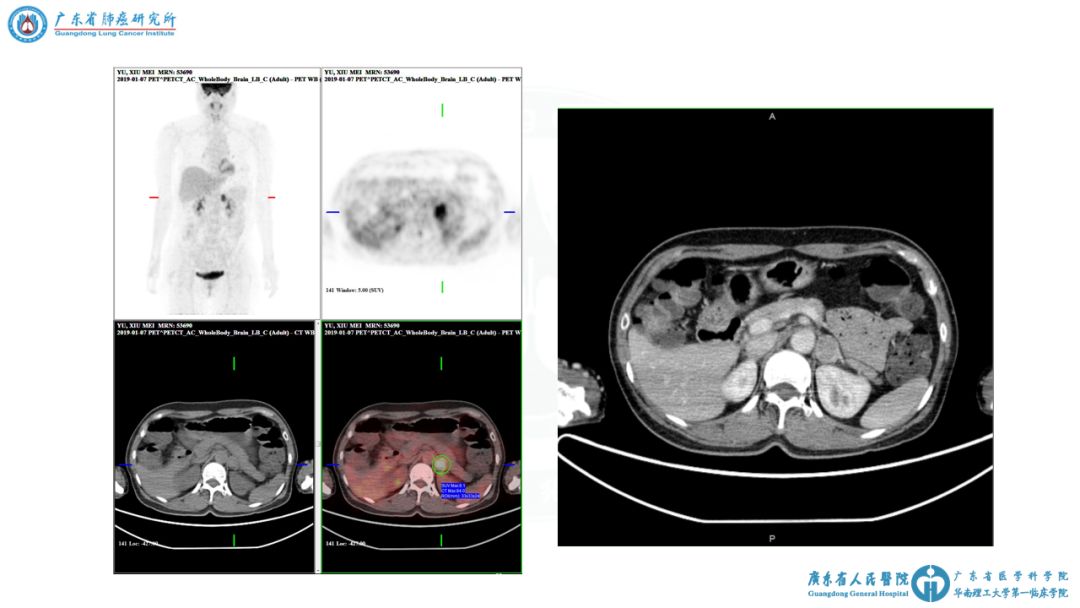

患者病史:2019-01-04 入院

图表资料

讨论要点2:多结节的寡转移?

1)患者目前诊断与分期

① 患者双肺多发病变是否为同时多原发癌?

② 患者肾上腺病灶是否为寡转移癌?

科内意见

① 双侧多原发肺癌伴左侧肾上腺转移,cT1b(m)N0M1b,IVa期。